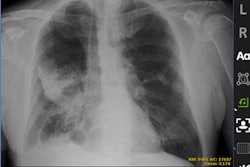

GE Healthcare has launched Thoracic Care Suite, a collection of eight artificial intelligence (AI) algorithms designed to detect abnormalities on chest x-rays -- including signs of pneumonia that could indicate COVID-19.

Thoracic Care Suite is a collection of eight AI applications developed by South Korean AI company Lunit that are designed to flag abnormalities for further review by radiologists. In addition to detecting pneumonia, they include applications for tuberculosis, atelectasis, calcification, cardiomegaly, fibrosis, mediastinal widening, lung nodule, and pleural effusion.

GE notes that Thoracic Care Suite gives radiologists support to identify high-risk cases as well as monitor patients and track the progression and regression of mild respiratory symptoms. The algorithms in the suite have an accuracy rate of 97%-99% as measured by the area under the curve (AUC), and one study resulted in a 34% reduction in radiologist reading time per case, according to GE.